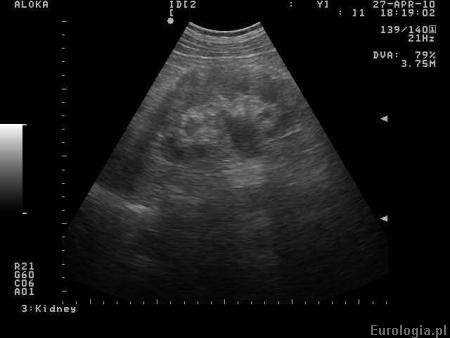

Fot. Poszerzony UKM u pacjenta z kolką nerkową - obraz USG prawej nerki.

Zastoinowo poszerzony UKM oznacza, że obraz układu kielichowo - miedniczkowego nerki sugeruje obecność utrudnionego spływu moczu z nerki do pęcherza moczowego. Obraz kliniczny oraz wywiad od pacjenta stanowią podstawę do ewentualnej dalszej diagnostyki. O przyczynach poszerzenia UKM można przeczytać w artykule: Poszerzenie UKM - przyczyny. Należy pamiętać, że zastoinowo poszerzony UKM w USG nie zawsze spowodowany jest przez utrudniony spływ moczu z nerki. Czasami torbiele pola centralnego nerki imitują zastój moczu w badaniu USG. Podstawowym badaniem wykonywanym w diagnostyce poszerzenia układu kielichowo - miedniczkowego jest urografia.